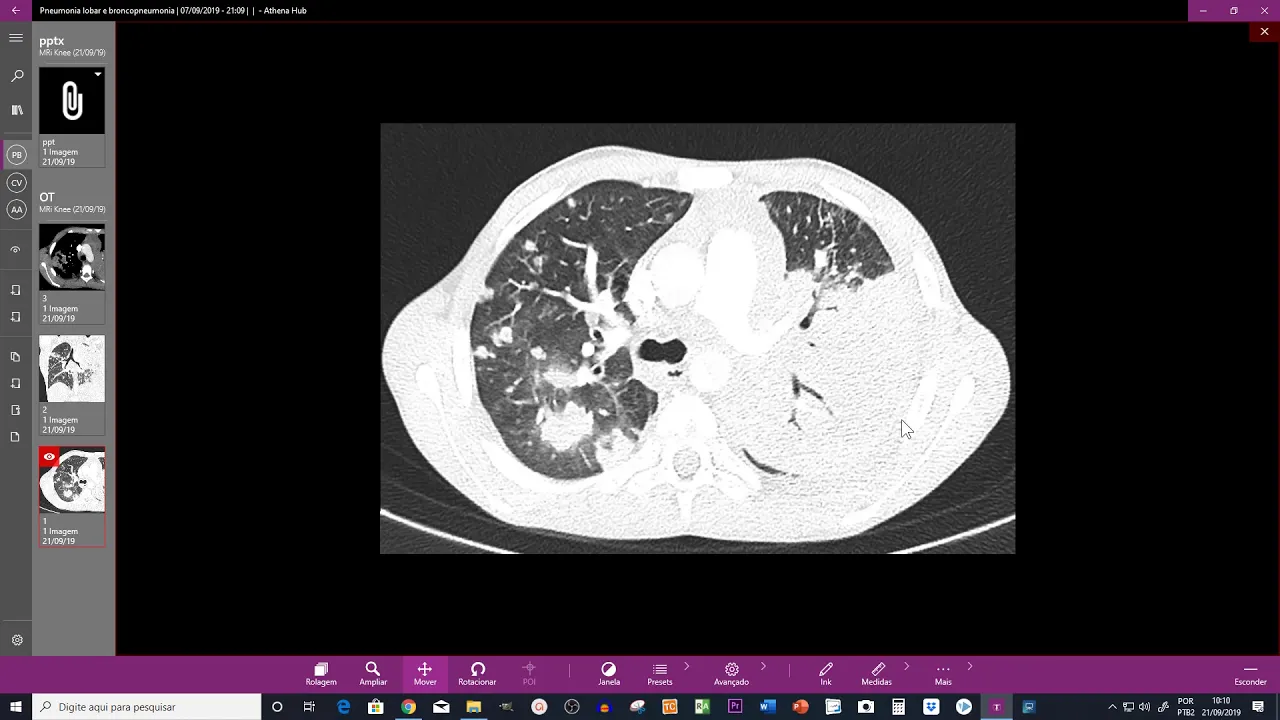

does so I constantly the similar positive virus cows visit AMS frequently up in ammonia in ammonia low bar mass existing orders tuberculosis my cuisine fart Pomona yeah 10 Oprah's is for example adenocarcinoma principalmente massino's principalmente degrees Mentos LAPD kou le positive image is automatically consolidation in matenda map in ammonia was informative a party room emergency million Terriers okay a necessary Collison clinic versus SEO trod give us a teen models mazhab cervical nor loosen saintly low Belarus thing is morphology the as a local is assume a local is a song center global are you have cervical

prossimo Branca is tapping shamed patent infringement Percy all those ovals address ain't is our head door you don't see the shadow in civil we dividing Sherry's odds of reality a consolidates environment are es nada shrunken through you perform arm consolidation Keenan des otro lado poor tanto estamos aqui na duo center Lobo Larry so console design center table desk on a low davido Fusco wall DVD escuela no específico de nada então você tem que ver o contest to clinic EST un contest cream grandpa sent a kumquat TIBCO de pinna Bonilla tip coda pnemonia addict reading comunidade

in town diagnosed rakia pnemonia low bar desta laden our key I scared ya delayed Bronco pnemonia the ins adamant a suspect nada Centro Belarus coma periphery in vitro fusco port on Thames on % company yellow bar a bronchopneumonia is mock resonance crew yatra porque vas a body tear my bacteria kikou Z as do squeezes yellow body bronchopneumonia happiness I cast on the old initial processing fixes so processing fixes initio Doretta maintenance of LCD Newman yellow bar the processing fixtures initial news Brancusi broom kill divide our ammonia okay a mice frequent cheeky opinion moon yellow bar

CA Pilipino moukaku eeeh broken ammonia protists bacterias in treating to be no more coke bodied RS do squeezes nest casa aramara pneumonia epidemic Alaska gravy avanzada aikido pod room deacons with the Sun low bar the new moon yellow bar yo padrón de Blanc pen ammonia very key no not a coaster Sun coral now comfy cow there I can request sankaranna a consolidation okay scared here's Posada this D bronchopneumonia D rate okay Antonis vida y sobre God the attempt Rossum